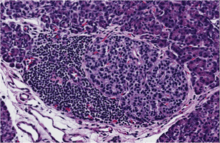

Type 1 diabetes (T1D) results from an autoimmune response against the insulin producing beta cells of the pancreas.

This destruction of beta cells causes patients to develop a lifelong dependence on insulin replacement therapy. Unfortunately, insulin injections are often insufficient for preventing many severe complications including heart disease, kidney failure, and blindness, among others. The disease process that leads to the development of T1D has been under investigation for more than 100 years. Several of the major players have been identified, but many key mechanisms of disease development remain undiscovered.[3]